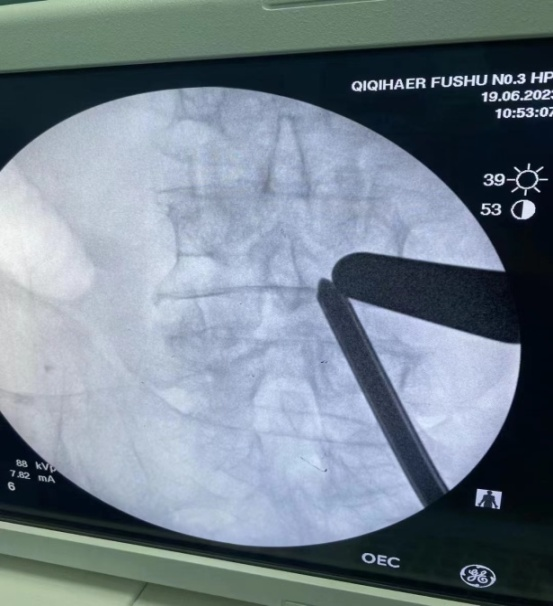

术中照片

手术是由负责人辛兆旭和助手赵越以及全体医生共同完成,创面只有两个1厘米的小切口。